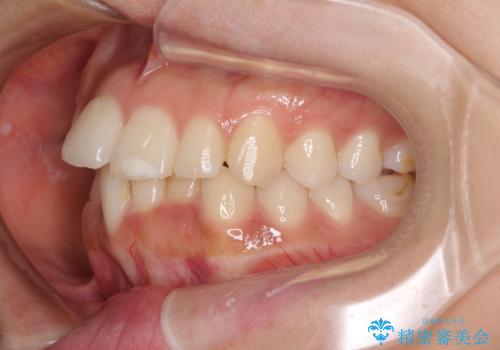

- 飛び出した前歯と全体的なデコボコを気にして来院された患者様です。

ワイヤーでもマウスピースでも治療可能でしたが、自己管理の重要なマウスピース矯正は自分には向かないとのことで、ワイヤー矯正で治療することとしました。

上下歯列全体を後方に移動させるため、親知らずは全て抜歯することにしました。